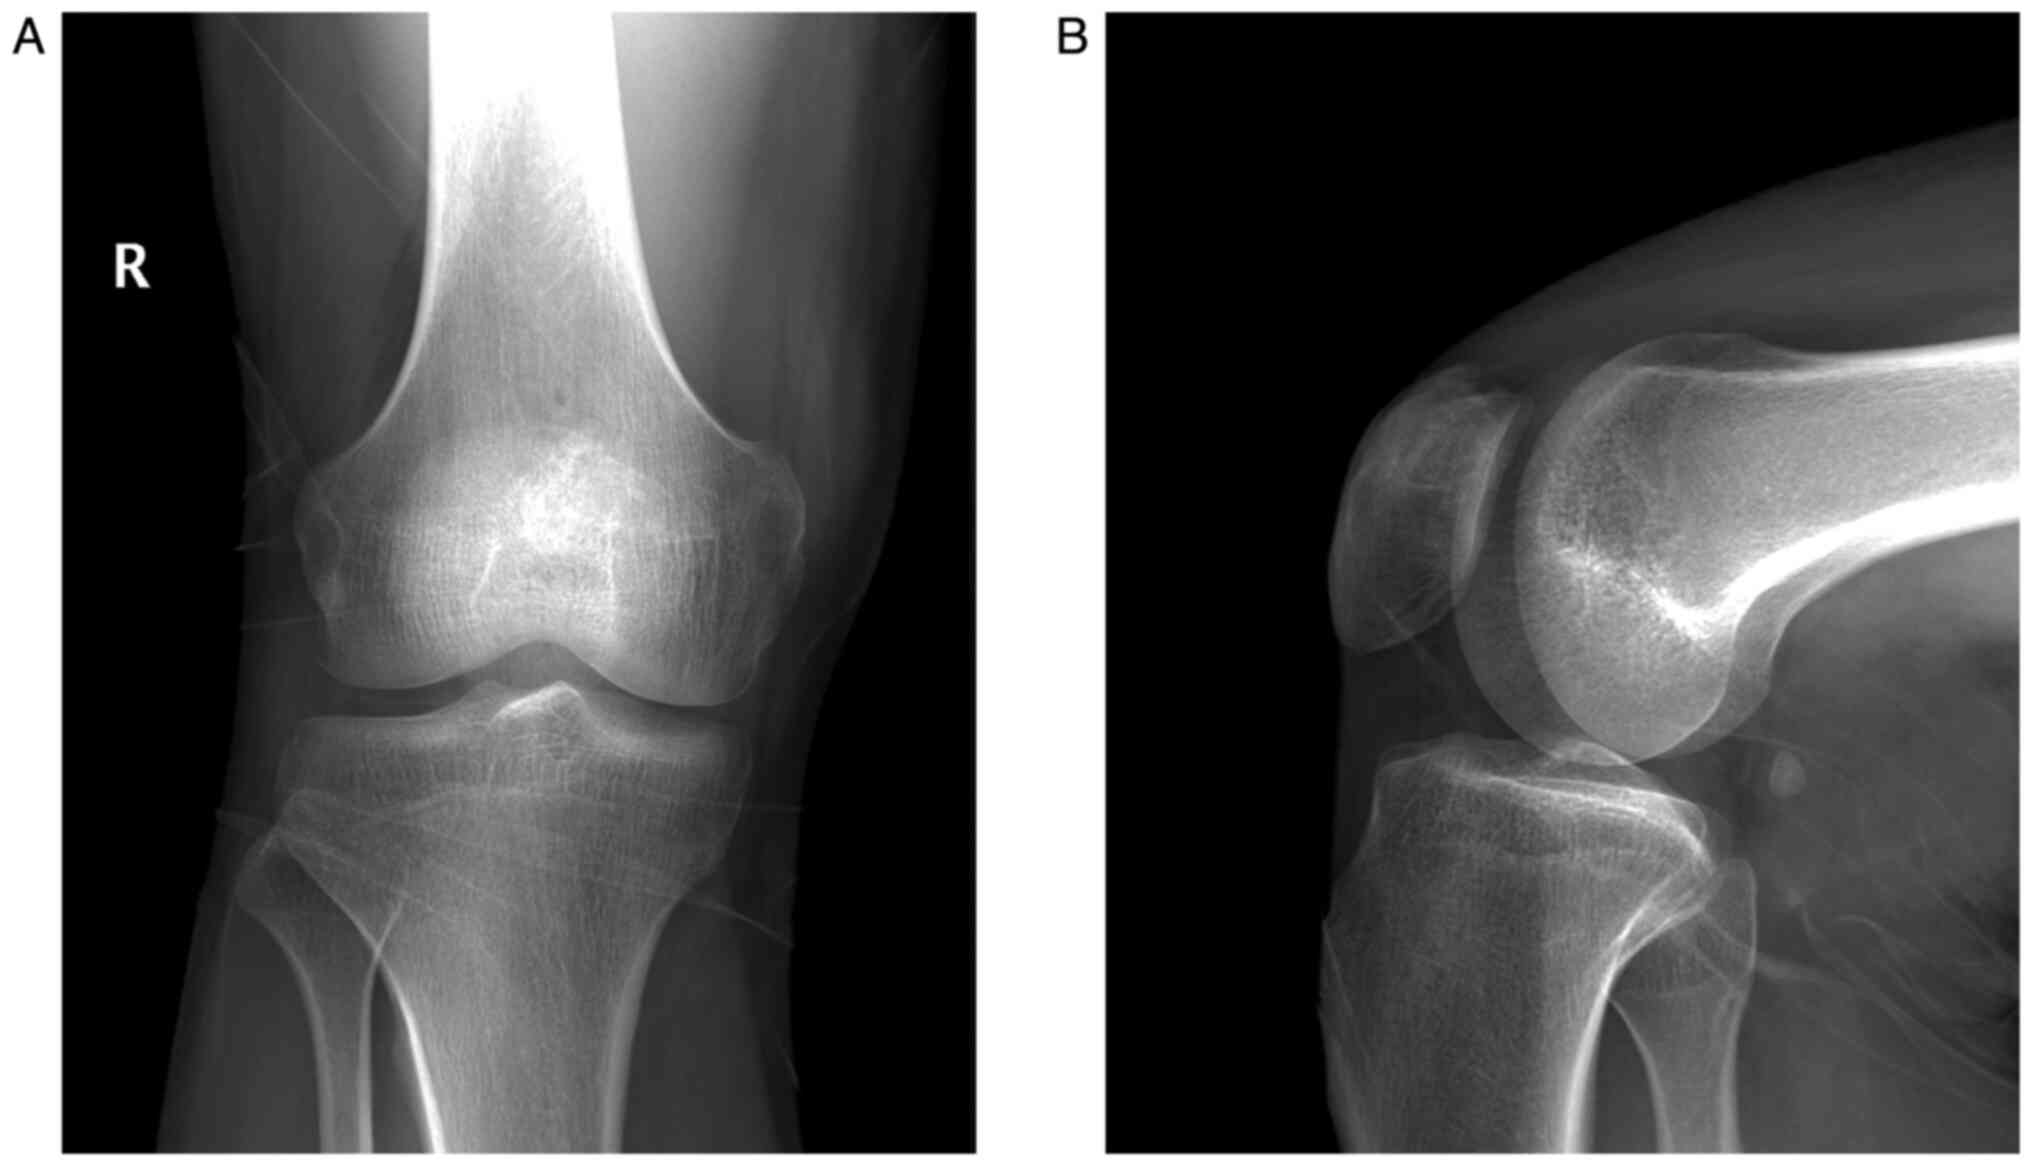

A 22-year-old male young adult was admitted to the 940th Hospital of Joint Logistics Support Force of Chinese People's Liberation Army (Lanzhou, Gansu, China) on December 5, 2020, with a 6-month history of intermittent pain in his right knee in absence of trauma. He did not have a significant personal or family medical history. His physical examination showed no obvious swelling or redness, and he had a normal skin temperature on the right knee. However, there was direct tenderness on the right patella. The range of motion of the right knee was full. The floating patella test, patella grind test, McMurray's test, anterior-posterior drawer test, and valgus-varus stress test were all negative. His neurological examination was normal. Laboratory tests revealed that his routine blood, liver function, kidney function, erythrocyte sedimentation rate, C-reactive protein, and tumor marker results were within the normal range. Radiography of the knee showed an osteolytic lesion at the medial superior quadrant of the right patella surrounded by a sclerotic margin with high density (Fig. 1). Computed tomography (CT) scan revealed a circular mixed-density image of the right patella that was surrounded by a thick sclerotic margin with high density (Fig. 2A). Three-dimensional CT showed no pathological fracture or cortical bone breakthrough (Fig. 2B and C). Magnetic resonance imaging (MRI) displayed a low-intensity signal mass on T1-weighted image (Fig. 3A) and high-intensity signal mass on T2-weighted image (Fig. 3B, C and D) with a well-defined lesion of the patella. Considering the clinical and imaging manifestations of the patient, benign bone lesions including chondroblastoma, osteoid osteoma, osteoblastoma, and bone abscess, were considered as the initial diagnosis.

Figure 1

X-ray images showing an osteolytic lesion at the medial superior quadrant of the right patella surrounded by a sclerotic margin with high density. (A) Anteroposterior plane, (B) Lateral plane.

The imaging manifestations of osteoblastoma differ depending on its location, and the results lack specificity. The most frequent X-ray manifestations of the osteoblastoma of the patella are that of an osteolytic lesion, with or without matrix mineralization and pathological fracture of the patella, surrounded by a high-density sclerotic margin with no evidence of extra-articular invasion (7,15). Aggressive spinal osteoblastoma can break through the bony cortex and invade the spinal canal and paravertebral soft tissue (16,17). CT scans are superior to MRI in showing calcification of osteoblastoma and thus are used to further confirm a well-defined lesion with fine calcifications. However, the radiological characteristics of CT are atypical. Tang P et al reported a case of osteoblastoma of the rib that was misdiagnosed as lymphomatous by CT and was confirmed by pathological examination (18). MRI helps in evaluating bone marrow edema and soft tissue component or extension of the tumor; however, there is no significant specificity to this finding.